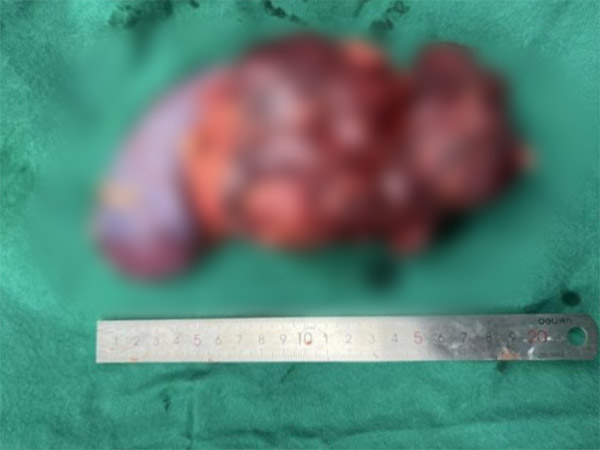

面对十二指肠来源、侵犯右肾的罕见巨大间质瘤,沈阳市第十人民医院(沈阳市胸科医院)普外科任庆华主任团队、泌尿外科李阳主任与麻醉科王涛主任团队强强联手,在肿瘤与升结肠、血管紧密缠绕的“手术禁区”中精准“拆弹”,不仅完整切除肿瘤,更成功保留患者升结肠!这场手术是多学科协作的典范,彰显了医院攻坚疑难重症的硬核实力。

肿瘤如“树根”般深扎于十二指肠、右肾及升结肠之间,稍有不慎便可能引发大出血或肠道损伤。任庆华主任团队凭借丰富经验,在复杂血管网中剥离肿瘤;李阳主任精细处理受侵肾脏组织,最大限度保留功能;麻醉科王涛团队全程护航,稳控生命体征。三学科无缝配合,最终在完整切除肿瘤的同时,奇迹般保住升结肠!